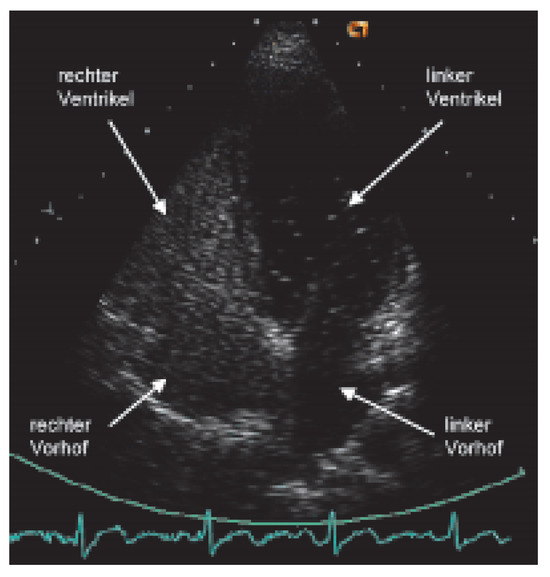

...und Immer Wieder Dieses Herzrasen!

by Michael K. Neuhaus, Hans o. Gloor, Marius Volkmer and Jürg Beer

Cardiovasc. Med. 2006, 9(6), 235; https://doi.org/10.4414/cvm.2006.01179 - 30 Jun 2006

Viewed by 51

Abstract

Ein 40jähriger Patient klagt seit 15 Jahren über rezidivierende tachykarde Palpitationen [...] Full article